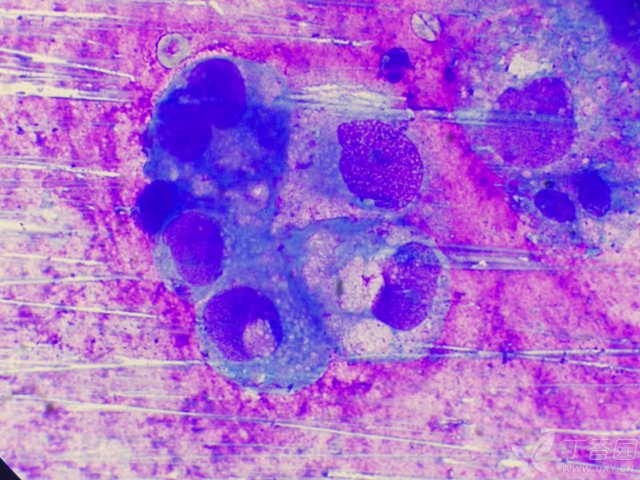

宠物肿瘤是什么、多可怕、能否治疗?一文揭秘!肿瘤是什么? 细胞生长失控之后,形成的团块就称之为肿瘤。肿瘤可以分为良性肿瘤和恶性肿瘤两种。 良性肿瘤是指不规则生长的细胞聚集成团块,与周围组织结合在一起,具有分界线没有侵犯周围组织。 恶性肿瘤是指突变基因失控,侵犯周围组织。 造成狗狗肿瘤的原因 引起肿瘤的原因很...

体内有恶性肿瘤的人,身体一般会有7个表现,平时多留意肿瘤可以分为良性及恶性两大类,通常情况下,良性肿瘤被称作“瘤”,而恶性肿瘤则被称作“癌”。 体内有恶性肿瘤的人 身体一般会有7个表现 体重无故下降: 恶性肿瘤细胞消耗体内的营养物质,导致患者在没有刻意节食或增加运动量的情况下体重明显下降。 持续性...